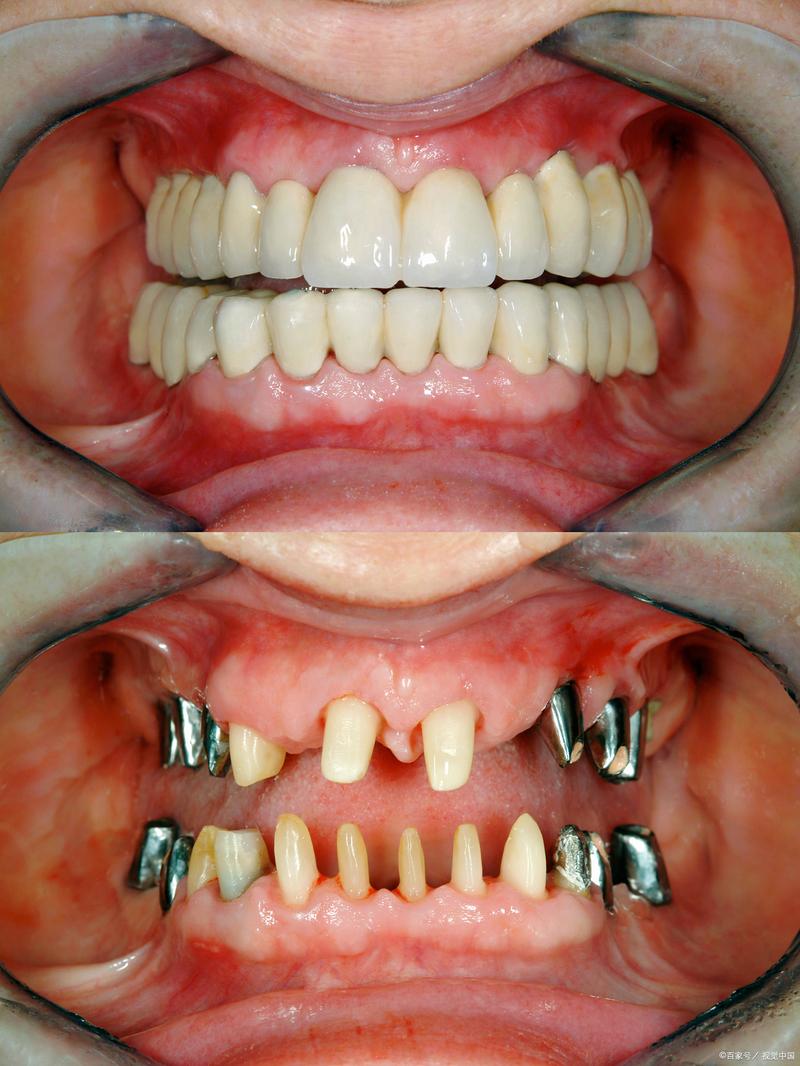

牙槽骨吸收严重确实给种植牙带来了挑战,但这并不意味着无法进行种植牙治疗,现代口腔种植学已经发展出多种技术来应对这种情况,以下是对严重牙槽骨吸收种植牙的详细分析和解决方案:

牙槽骨吸收严重虽然增加了种植牙的难度和复杂性,但通过现代的骨增量技术(如自体骨移植、GBR、上颌窦提升等)以及短种植体、倾斜种植体等替代方案,绝大多数患者最终都能成功获得功能良好、美观耐用的种植修复体。